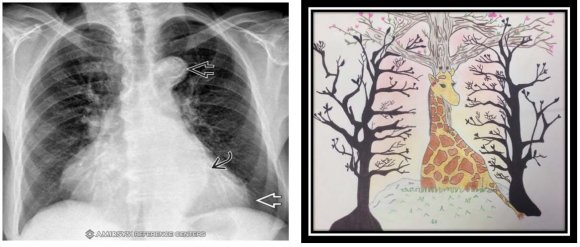

One of the areas with the most problems in primary health care is Radiology, where the proper use of resources for making decisions with diagnostic images becomes crucial. Because of this, it is of vital importance that the primary care physician learn to optimize health resources by requesting and interpreting the most important diagnostic images in their area of work. Therefore, in Bogotá, Colombia, a didactic tool based on the schematic drawing for learning in the area of Radiology called RADIARTE has been created by the researcher. This tool is developed in an elective matter that seeks to correlate the imaging findings of the most prevalent diseases to which the primary care physician will be confronted using conceptual associations with drawings created by the students in the development of the subject. The evaluation method used is through equipment and evaluation of the transmission of ideas in an appropriate learning environment an art exhibition where students from other careers, teaching specialists and radiologists assess the information transmitted through the use of drawing. With this tool, they develop skills in meaningful learning, teamwork, and evaluation of the transmission of ideas in an appropriate learning environment (Figure 1-4). Chest x-ray in AP (anteroposterior) view with severe aortic stenosis and cardiac dilation. A radiopaque image is observed in the apex cardiac caused by concentric ventricular hypertrophy (white arrow), and a tortuosity in the aorta with the presence of calcification (black arrows). In the drawing, the prominence of the aortic arch with the head of the giraffe is interpreted, while its body interprets the hypertrophy of the left ventricle. Likewise, the bony structures are interpreted with the branches of the trees. Image is taken from Amirsys by university platform. Magnetic resonance of the knee in coronal section with the presence of multiseptated para meniscal cysts with medial horizontal meniscal lesions. In the drawing, the femoral condyle is interpreted through the eyes of the owl. Likewise, the cruciate ligaments are interpreted by the owl's beak and the tibia using the neck of the owl. Image is taken from Amirsys by university platform. The systematic review of the literature by the researcher shows the evidence of this didactic tool in related areas such as anatomy with positive quantitative results. However, in the area of Radiology, it has not been demonstrated that there are sensorial perceptions that students have with this tool for meaningful learning. For this reason, the present study focused on determining the sensory perceptions of the tenthsemester medical students of the faculty of health sciences at the Rosario Unevirsity with the Radiarte teaching tool (Radiología desde el arte) in the area of radiology. Through qualitative research with an ethnographic approach.